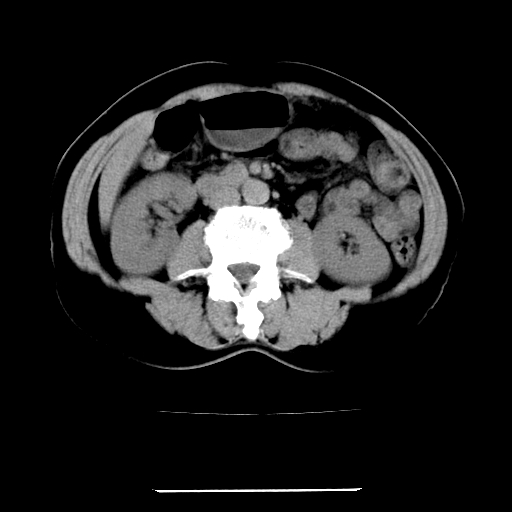

标题: CT22301:女,67岁,上腹部疼痛一周伴皮肤黄染,无发热。 [打印本页]

女,67岁,上腹部疼痛一周伴皮肤黄染,无发热。

左叶肝内胆管结石,并远端肝内胆管扩张。

考虑:肝内胆管结石继发肝内胆管扩张,右肾旋转不良。

肝内外胆管结石并肝内胆管扩张。

肝内外胆管结石并肝内胆管扩张

肝内外胆管扩张,左叶胆管内结石

建议薄层观察,除外肝门部胆管细胞癌

考虑肝胆管癌;胰头占位?【形态失常,体积增大】

1、肝门高密度影下层面和胰头层面可见轻度胆管扩张,而静脉和延迟期均未见扫描完胰头,不能完全排除胰头占位。2、肝门部高密度影,考虑钙化或结石。

考虑肝门胆管癌伴门脉左支受侵包埋,建议mrcp进一步检查。

肝内胆管结石并胆管扩张